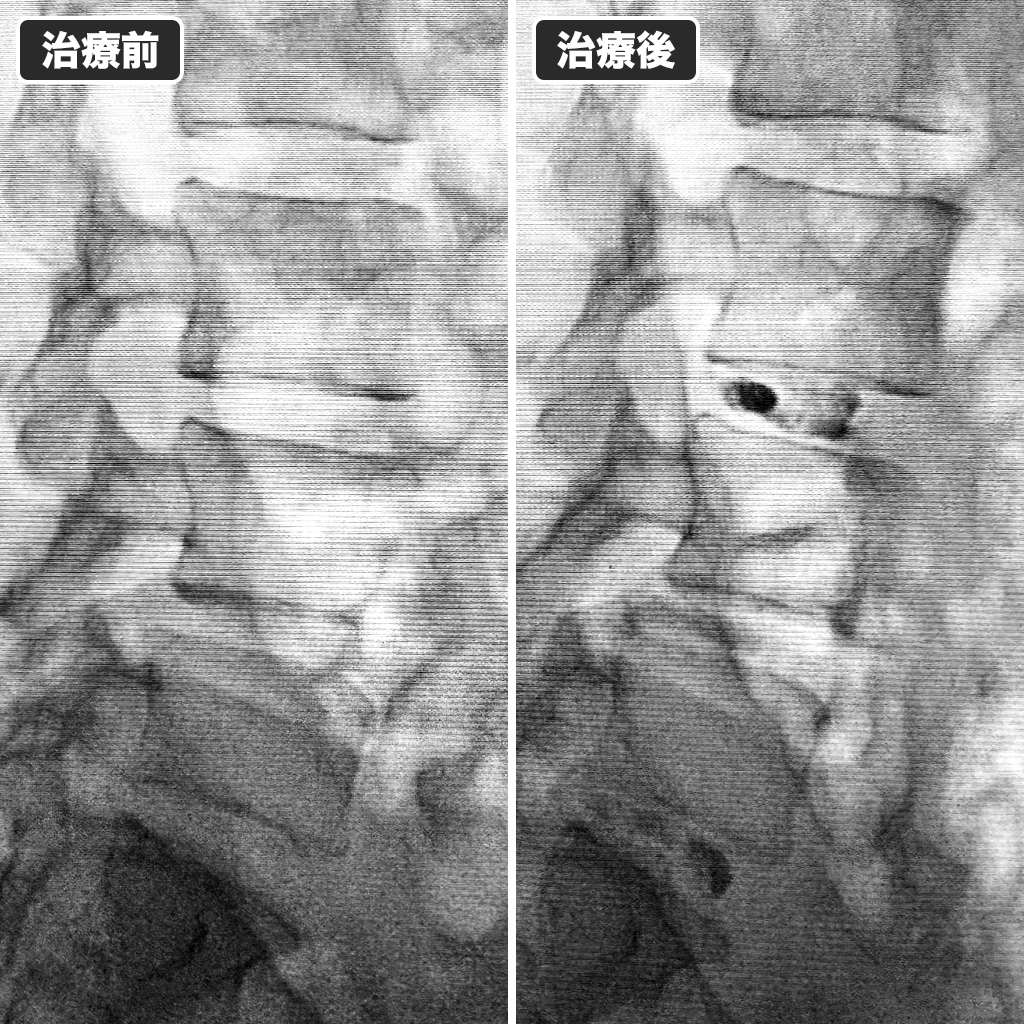

治療前後のレントゲン写真

治療前後のレントゲン写真です。左側が治療前、右側が治療後になります。今年8月に神経障害が出現したばかりですので、完治するはずだとご説明しました。